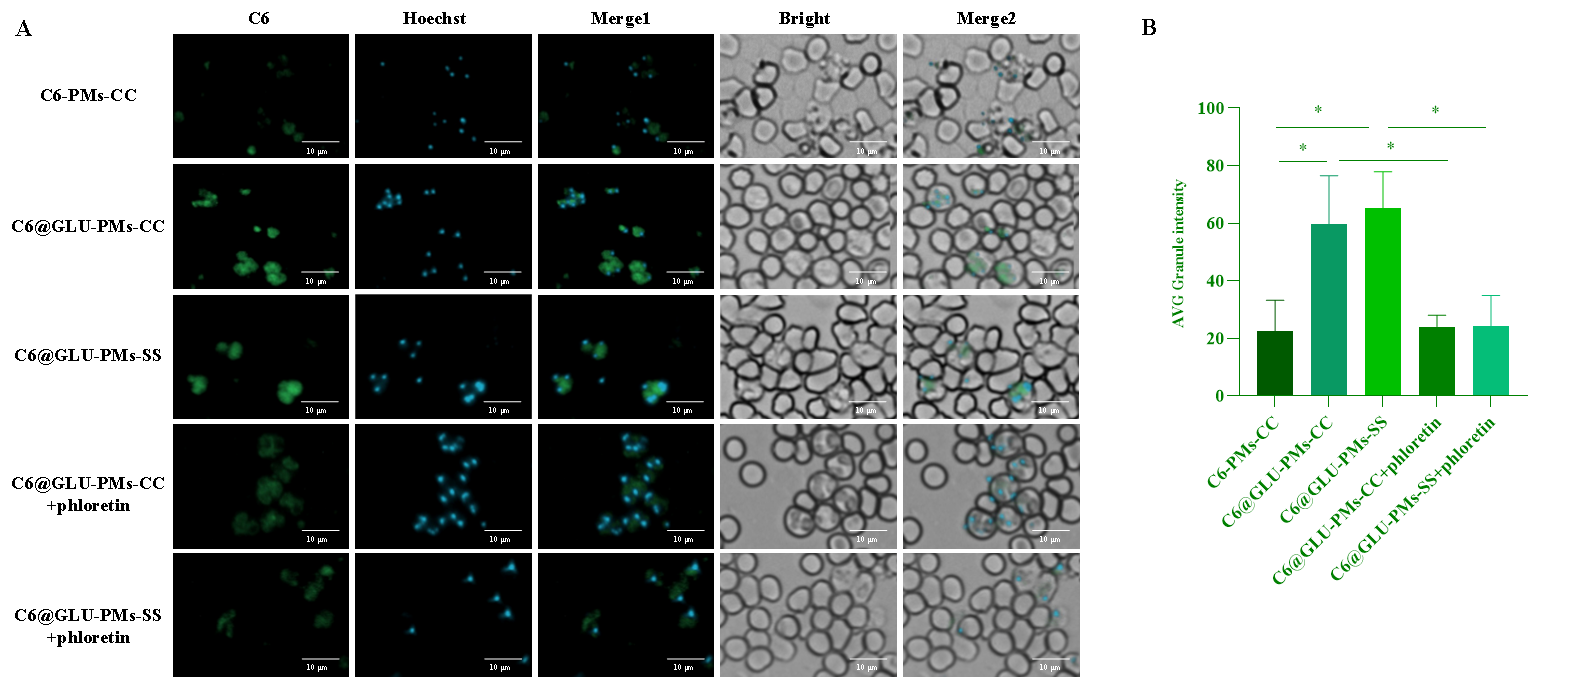

图2 C6-PMs-CC��、C6@GLU-PMs-CC和C6@GLU-PMs-SS的体外靶向性(A����、B)和红细胞内靶向性(C)评价(n = 3)

以香豆素6(C6)标记的无葡萄糖基修饰的非还原响应微粒(C6-PMs-CC)为对照���,微粒与感染的红细胞共孵育后����,葡萄糖基修饰微粒在疟原虫中的富集显著增强(P<0.05)(图2)���。